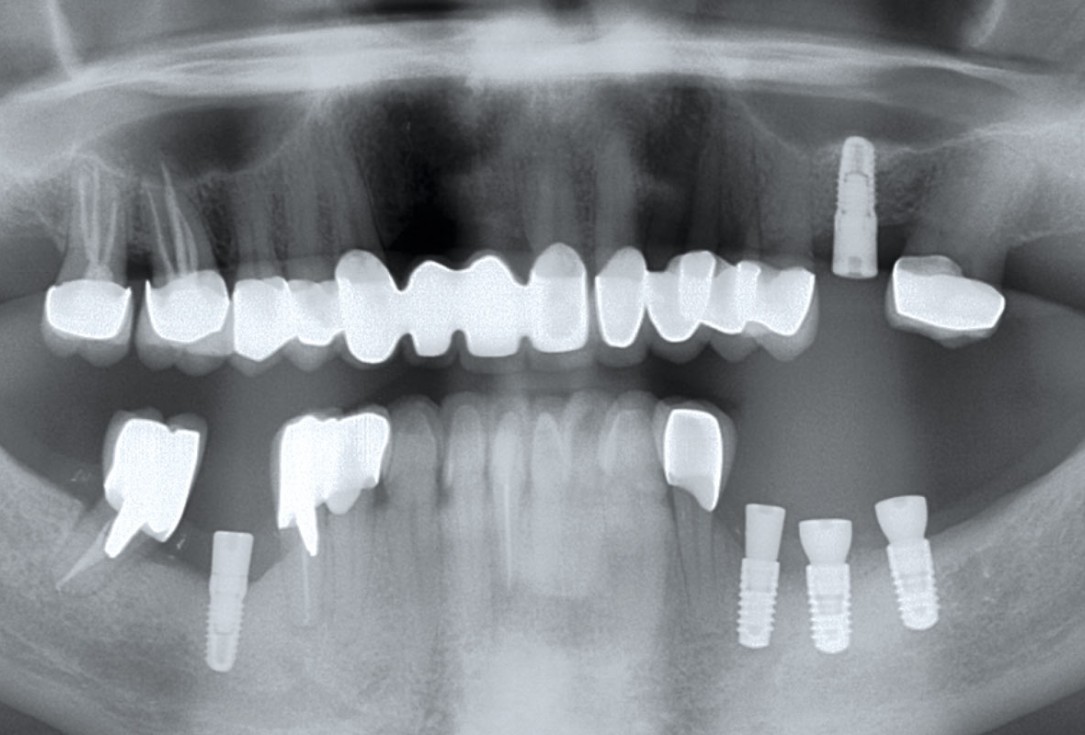

12/12 - 17 months post-operative: stable bone situation

Ridge augmentation in the mandible with maxgraft® bonebuilder in a free-end situation - Dr. Dr. Dr. O. Blume